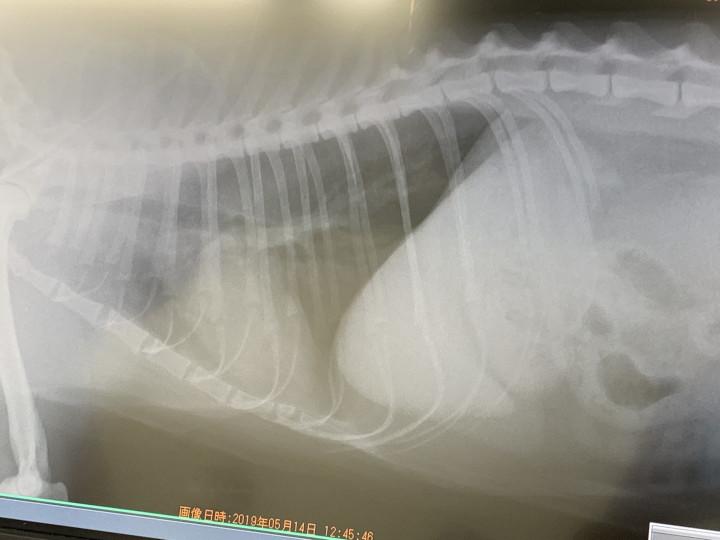

で、お姉さんの病院で、なんとなくの不安要素を説明して、レントゲンと血液検査。

こんな感じでした。

これは画像診断が苦手な私でもわかる。

これだけはっきり器官が映ってるのは

「気管支炎ですね〜」

ですよね〜。

「食道や肺には炎症は見られません。心臓も肥大はなくて、今は落ち着いてますね」